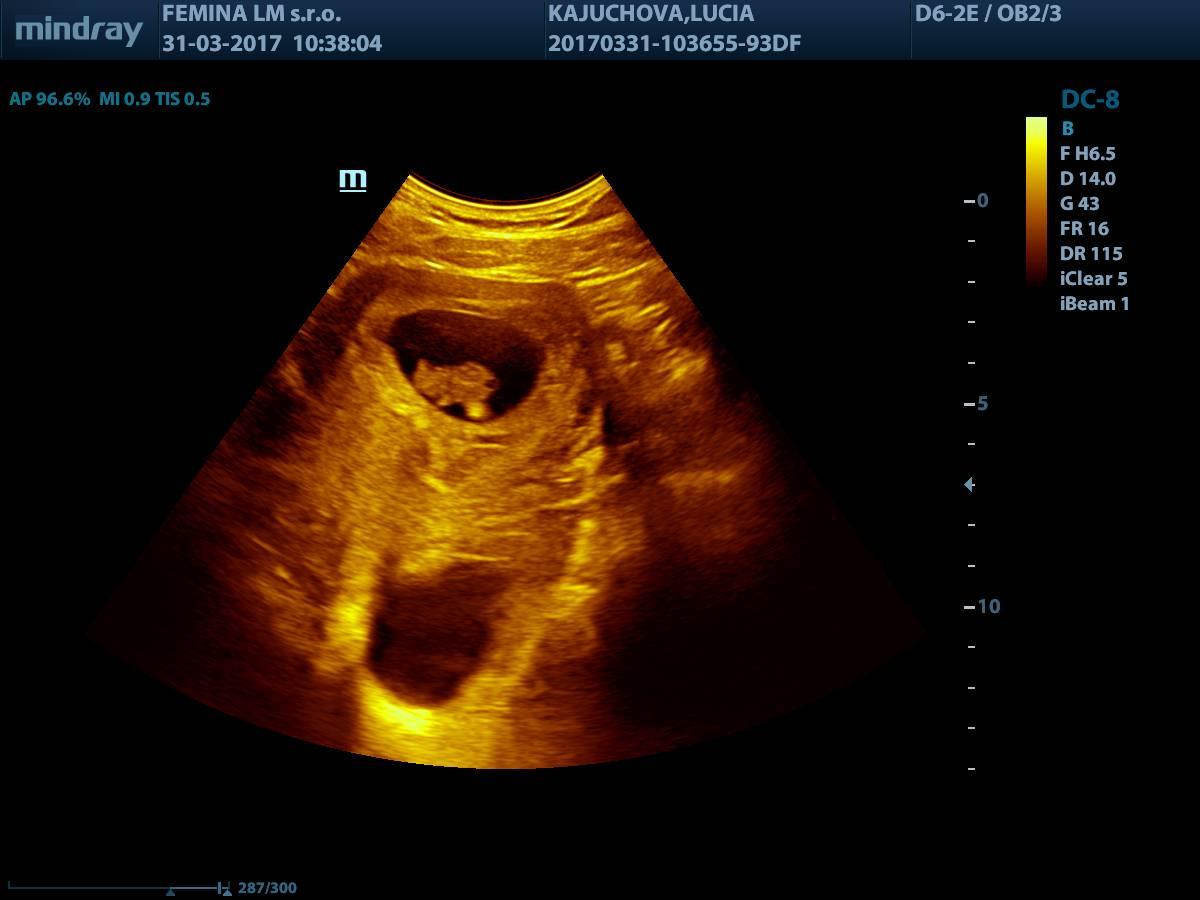

@sasenka04 ta je krasnucka babika...Som rada, ze je vsetko o.k. a verim, ze sa este otoci, treba jej navecer svietit silnou baterkou dole u Teba na brusku, mozno sa otoci za svetlom...Znie to ako blbina, no ked som cakala prveho syna a chodila som na stretnutia ohladom vsetkeho, co sa tyka babätiek, ohladom porodu, kojenia atd, tak tam sa toto riesilo, ze co robit, ak dieta je KP a jeden par, co tam boli to tam prezentovali, zevraj svietili baterkou a babätko sa im takto otocilo do polohy hlavickou dole 😉...No poskusaj, co sa da, snad sa princezna este otoci...Drzim palceky 🙂